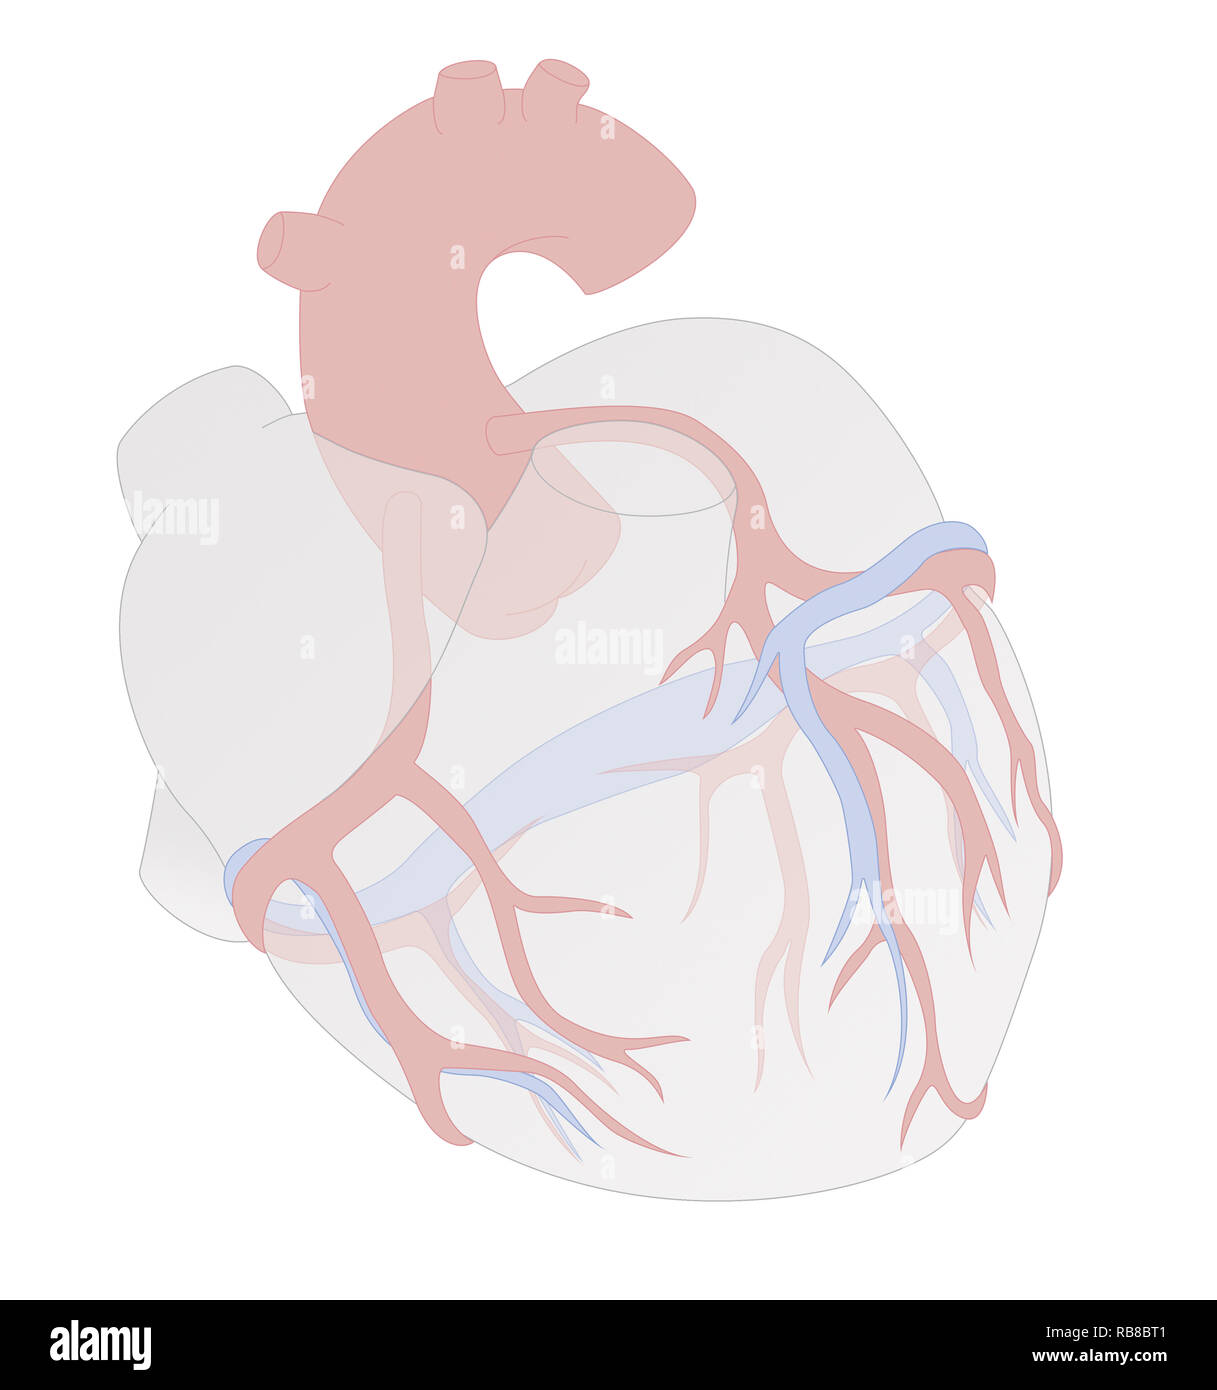

HEART, ILLUSTRATION Stock Photohttps://www.alamy.com/image-license-details/?v=1https://www.alamy.com/heart-illustration-image230680913.html

HEART, ILLUSTRATION Stock Photohttps://www.alamy.com/image-license-details/?v=1https://www.alamy.com/heart-illustration-image230680913.htmlRMRB8BT1–HEART, ILLUSTRATION